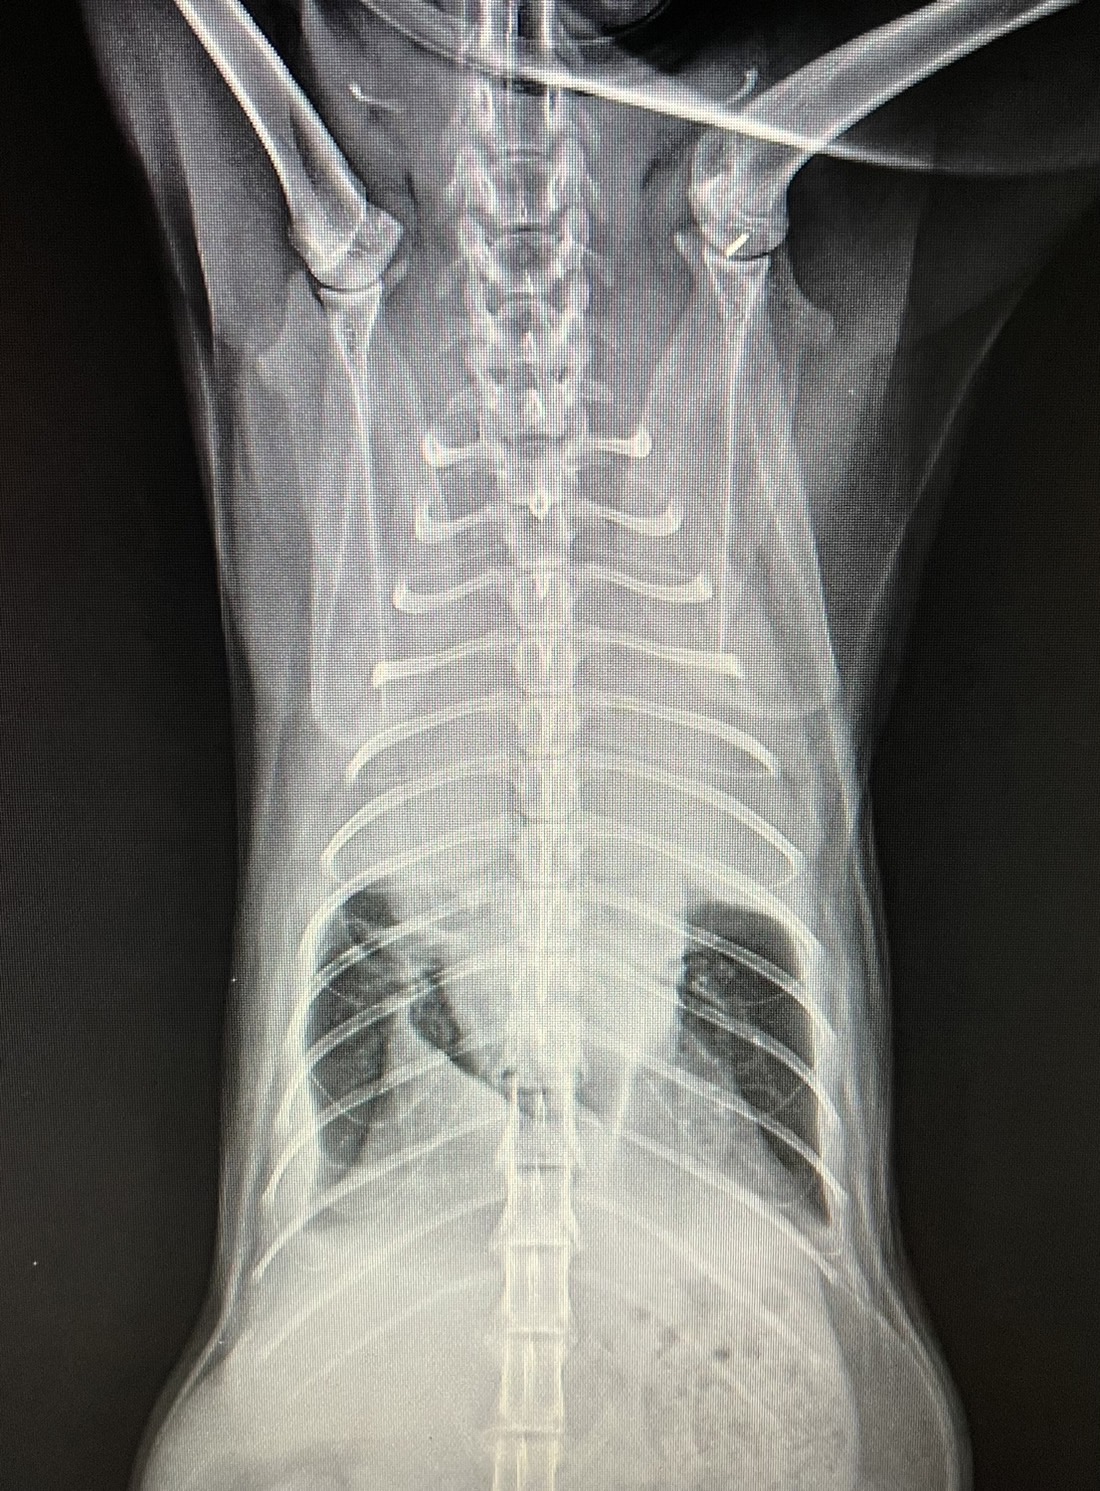

胸腔內有許多重要的器官,其中包含了肺臟。

胸腔內若因為疾病而產生胸水,

導致肺臟的擴張受限、呼吸功能異常,

甚至可能缺氧造成無法挽回的後果。

一般我們將胸腔內的積液統稱為胸水,

胸水的成因有很多種,一旦發現胸水,需要抽出胸腔內液體,

不但可以緩解動物呼吸困難的狀況,

最重要的是可將液體進行分析,視情況需同時進行其他全身檢查,

例如血液學檢查、X光檢查、超音波檢查…,才能找到胸水產生的原因,針對病因進行治療。

若是單純抽出胸水,而沒有找到原因,胸水持續產生會讓動物反覆陷入缺氧的危險當中。